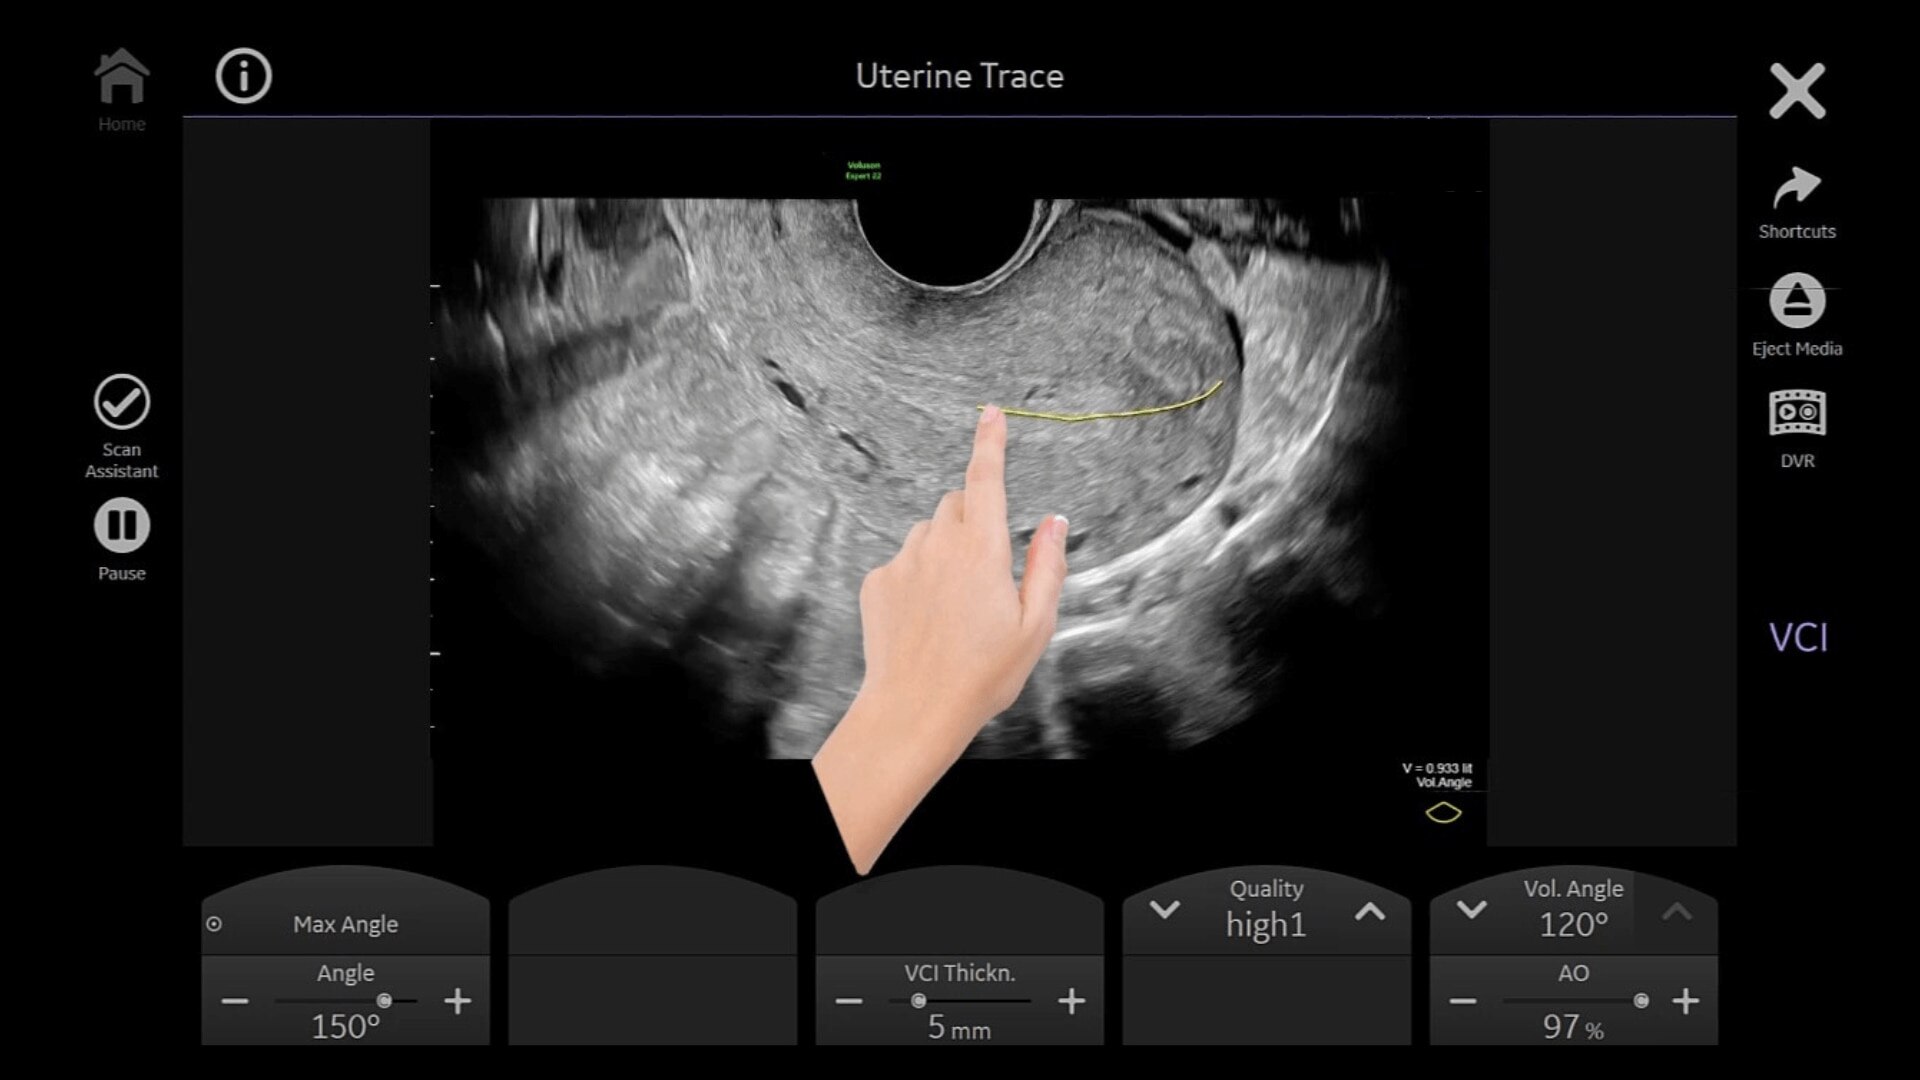

Uterine Trace

Easy display coronal view of uterus.

• Uterine Trace acquires the volume & then displays the coronal view of the uterus to simplify identification & reporting of uterine malformations.

• Easy, accessible 3D for simple, efficient gynecology exams

• Adding 3D can provide more information to help inform your diagnosis and treatment plan. With a comprehensive set of 3D tools, you’ll have everything you need to easily obtain views not possible with standard 2D views.